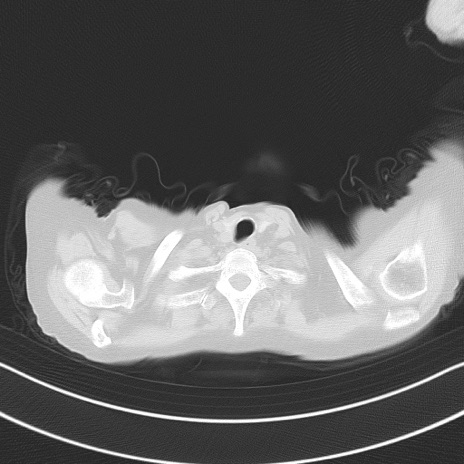

症例40(横断像)他院1日前

横断像

他院CT